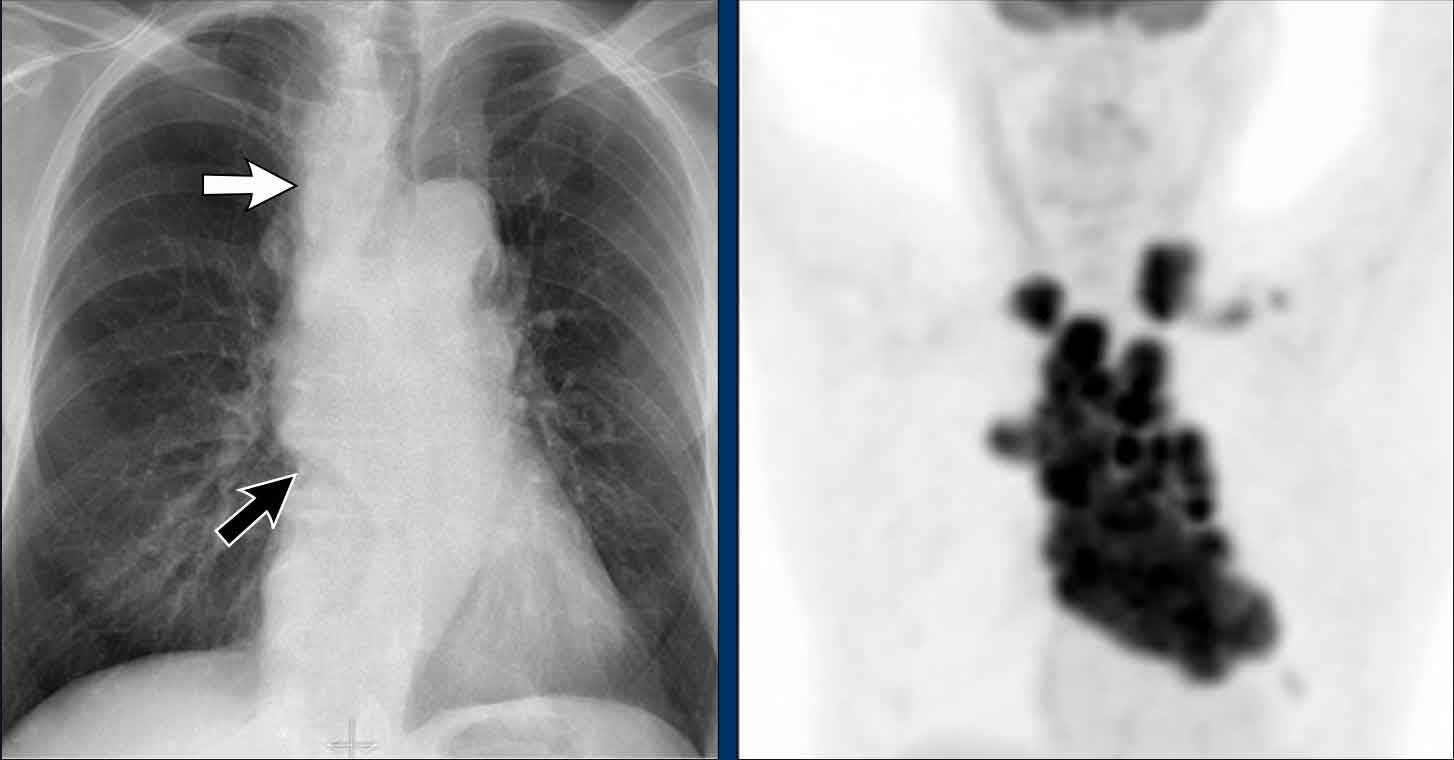

Displacement of the Azygoesophageal Line (2) – Subcarinal Lymphadenopathy

A common cause of displacement of the azygoesophageal line is subcarinal lymphadenopathy (station 7).

On the chest X-ray, note superior displacement of the azygoesophageal line just below the carina, consistent with enlarged subcarinal lymph nodes (black arrow).

Additional right paratracheal lymphadenopathy is seen, displacing the right paratracheal stripe (white arrow) and deviating the trachea to the left.

Continue with PET-CT...

PET Imaging

• PET-CT demonstrates extensive hypermetabolic lymphadenopathy in the mediastinum and neck, which is more conspicuous than on chest radiography.

• Cervical lymph nodes are involved—an important finding as they are accessible for biopsy.